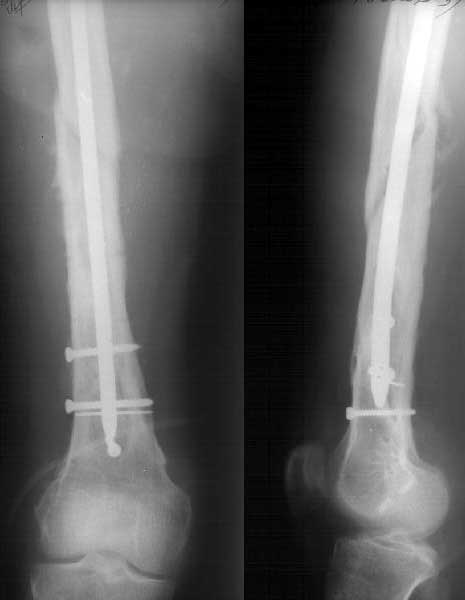

Глубокоуважаемые коллеги, Пациент 22 лет, 2,5 года назад оперирован у нас в институте по поводу низкого перелома бедра. Пару недель назад упал навзничь, поскользнувшись. Сломал бедро выше пластинки - снимок в приложении.Как бы вы поступили в данном случае?Если бы пластинку удалили сразу после сращения, интересно, предотвратило бы это подобный перелом? -- Best regards, Alexander N. Chelnokov

Удалили пластинку из двух доступов, винтик и спицу оставили. Сделан закрытый интрамедуллярный остеосинтез без рассверливания, прошло без

особенностей, стержень взял покороче, чтобы только до винта дошел. Снимок в приложении.

Кликните для загрузки файла 2k20309a.jpg

19KB (19793 bytes)

AC> Удалили пластинку из двух доступов, винтик и спицу оставили. Сделан

AC> закрытый интрамедуллярный остеосинтез без рассверливания, прошло без

AC> особенностей, стержень взял покороче, чтобы только до винта дошел.

AC> Снимок в приложении.

Хорошо получилось. Стержень только кажется тонковатым.

a> Хорошо получилось. Стержень только кажется тонковатым.

Спасибо. Стержень действительно всего 10 мм, но из-за винтов выше и ниже ничего никуда не денется. Тут и 11 (это максимальный диаметр

имеющихся у нас UFN) не заполнил бы канал, для этого надо было бы стержень 14-15 мм. В таком стержне можно и блокирующие винты разместить не 5 мм, а потолще, тогда можно было бы полную нагрузку разрешать сразу. Но у нас такого диаметра есть только старые 4-гранные, штыковидные. В принципе, можно и в них дырок наделать, мы штук 15 таких ввели, но 11-12 мм, и только 2 - 13 мм. Поскольку разверток гибких пока нет.